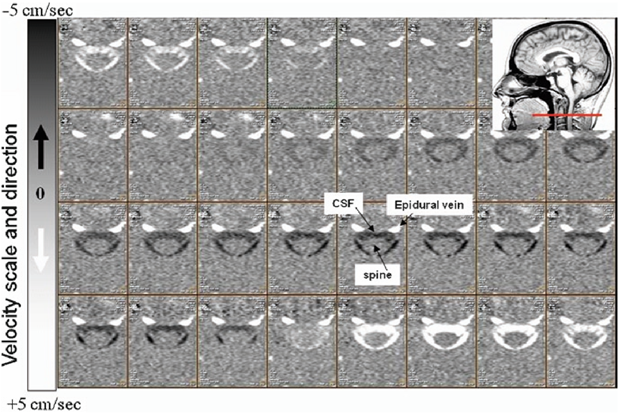

磁共振检查测量脑脊液流动速度,就如同检查MRA一样,磁共振利用垂直于磁共振扫描面的液体流动,在磁共振不同时像信号的不同,经过一个心跳周期,液体流动的变化可以通过影像计算其流速,一个心跳周期32幅影像。如下图,通过流速敏感软件测量后,我们就了解局部脑脊液流速。把这些局部流速数据模拟成每个心跳周期的液体流动,我们就可以动态的看到脑脊液大概的动力学运动情况,来判断动力学存在不存在问题了。